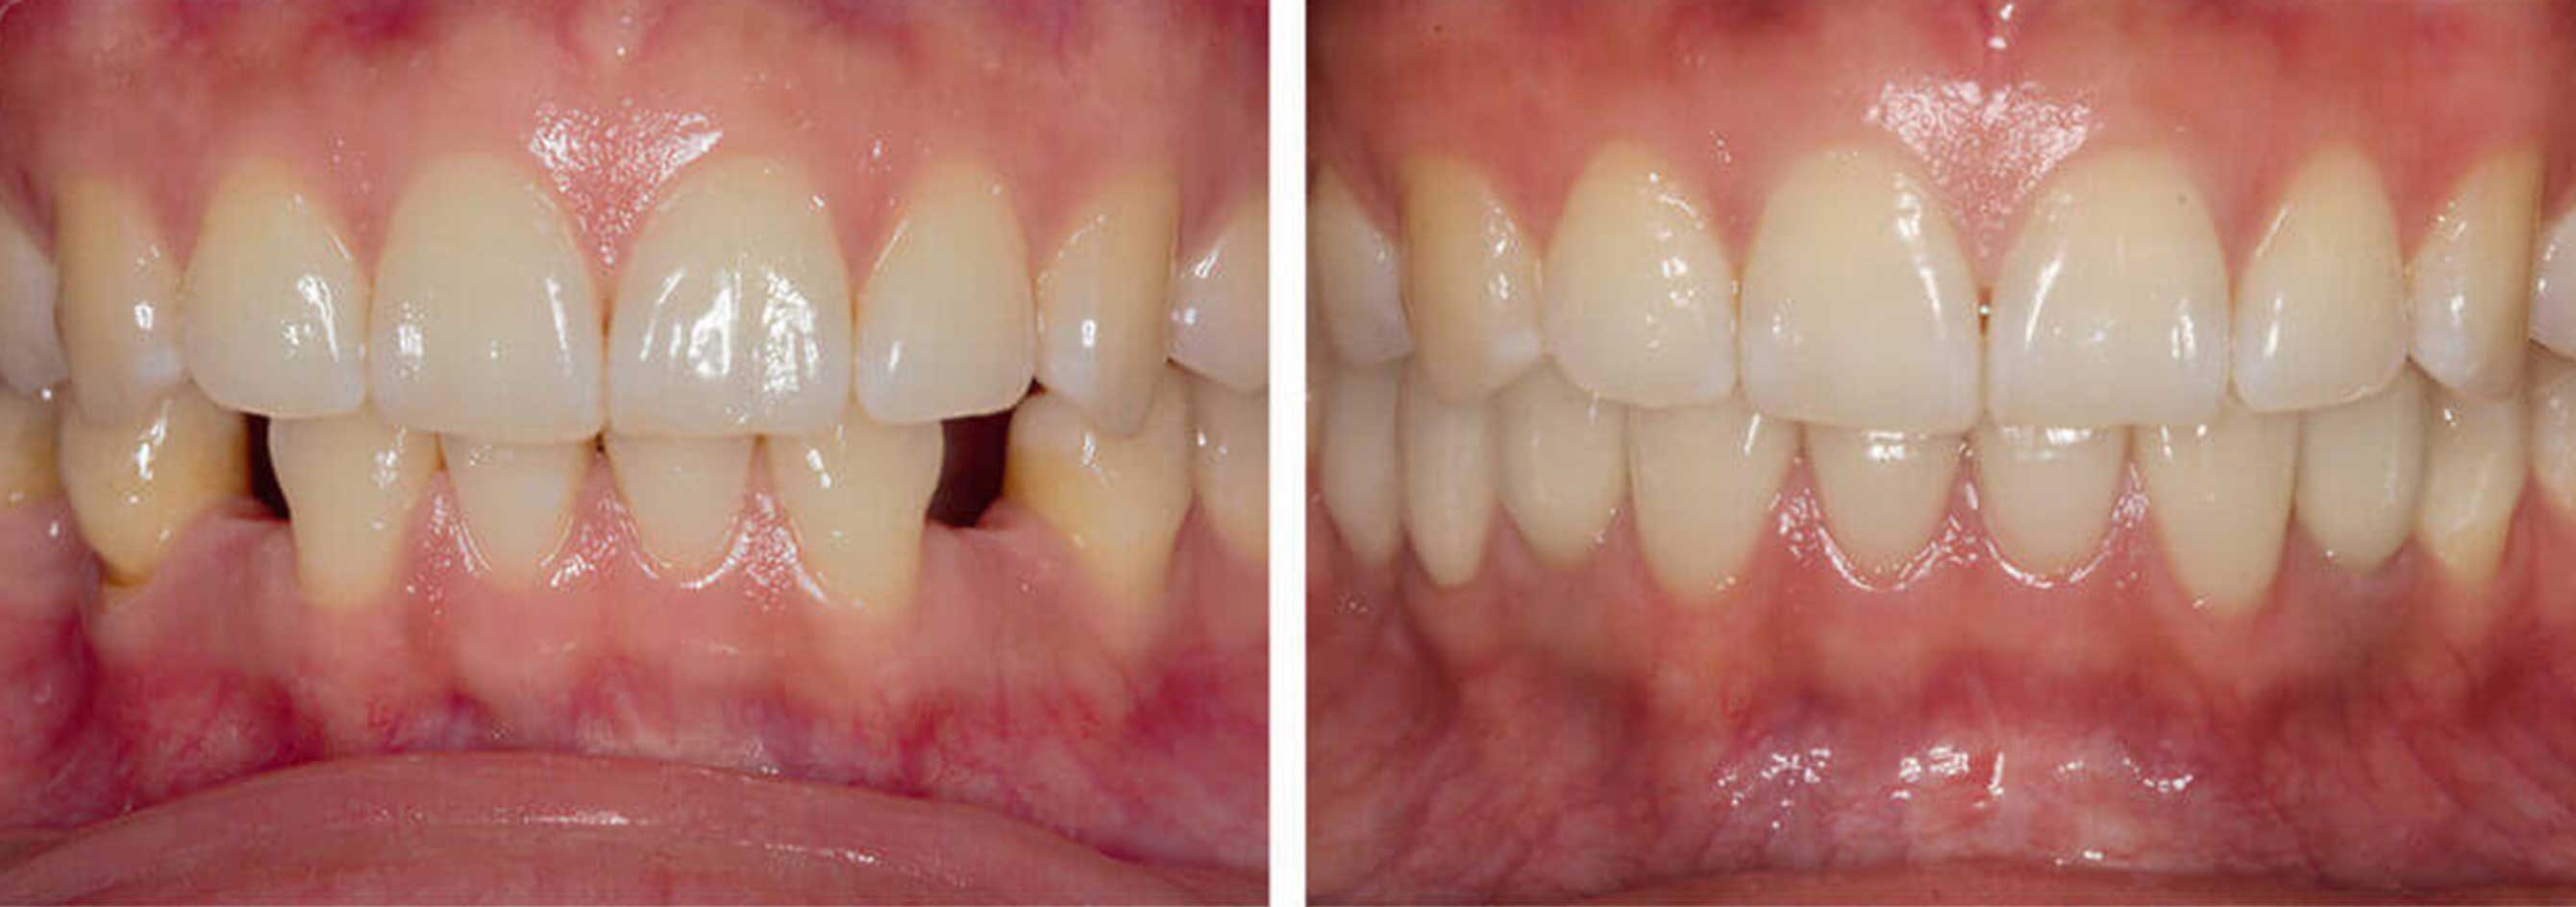

Das Resultat überzeugt

- Beschleifen gesunder Nachbarzähne entfällt

- Problemloses Kauen und Sprechen

- Kein Fremdkörpergefühl

- Störende Halteklammern entfallen

- Kein Kieferknochenabbau

- Gute Ästhetik